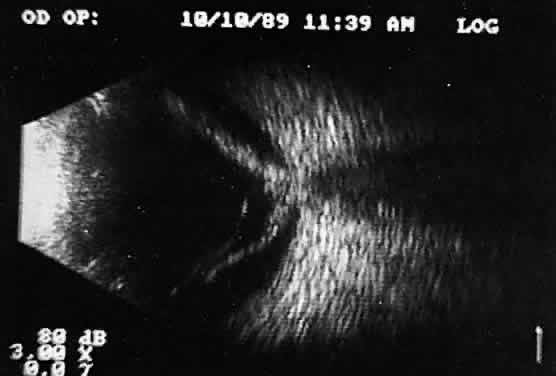

POSTERIOR VITREORETINAL INTERFACE EVALUATION

Recent improvements in image quality and fused, real-time display have made ultrasound image interpretation easier for every ultrasonographer. Visualization of subtle changes such as movement and recognition of the posterior formed vitreous hyaloid are now possible, even in clear media situations. These clear vitreous structures, which are often exceedingly difficult to appreciate optically, can be recognized ultrasonically after a relatively short period of training (Fig. 17). Clinically, establishing the position of the posterior hyaloid is important in evaluating a variety of vitreous retinal disorders, such as macular holes, tractional detachments, and partial or complete vitreous separations.16,17

Fig. 17. Contact B-scan: posterior formed vitreous face separation, with prominent Weiss ring evident.